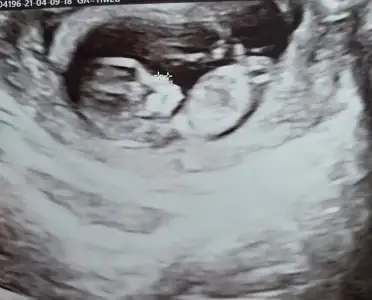

Ikra meyra Ikra meyra 11 haftalik bana da tahmin de bulunurmusunuz nub tam olarak neresi ben pek anlamadim :)

• BeautyPlus_20210409151800057_save.webp

BeautyPlus_20210409151800057_save.webp

28,1 KB · Görüntüleme: 64

• Screenshot_20210409-162230_Video Player.webp

Screenshot_20210409-162230_Video Player.webp

27,9 KB · Görüntüleme: 66